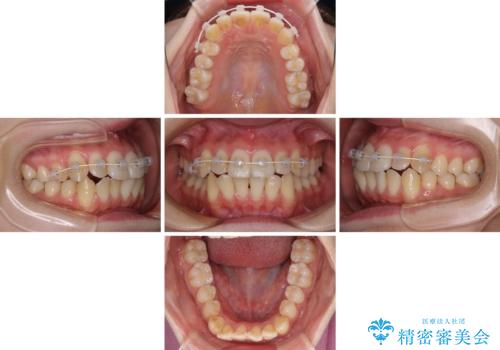

- インビザライン

- 1年5ヶ月

舌側転位している側切歯特有の、切縁の位置が不揃いであったり、根元が内側に引っ込んだ状態であったりという、インビザライン独特の仕上がりになることなく、きれいに整った歯列とすることができました。